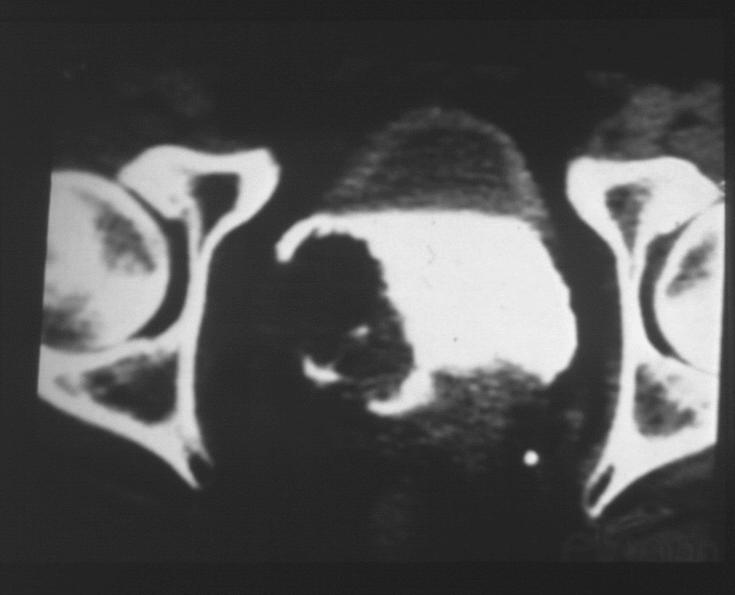

La TAC con mezzo di  contrasto permette di valutare tutto l'apparato urinario, l'eventuale presenza di lesioni , interessamenti linfonodali e secondarietà; lesini vescicali piccole o piatte possono sfuggire alla TAC e quindi, in presenza di forte sospetto, è bene concludere l'iter diagnostico con un controllo con cistoscopia.